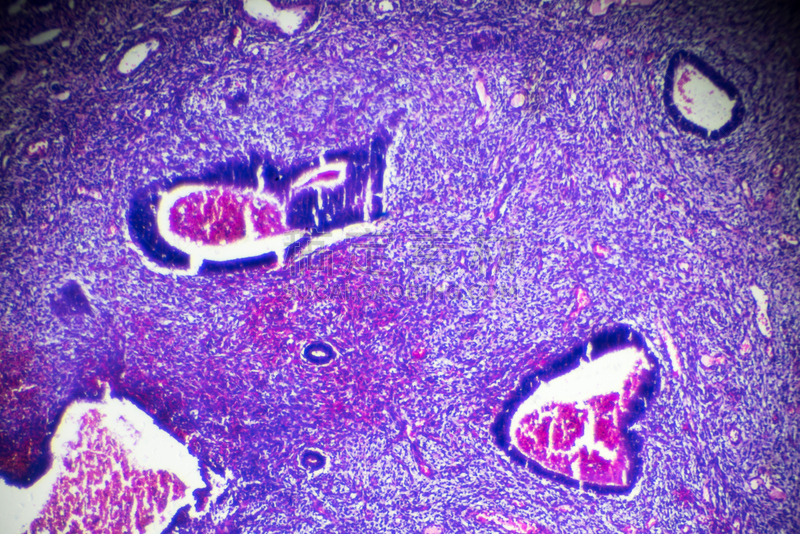

结缔组织详情